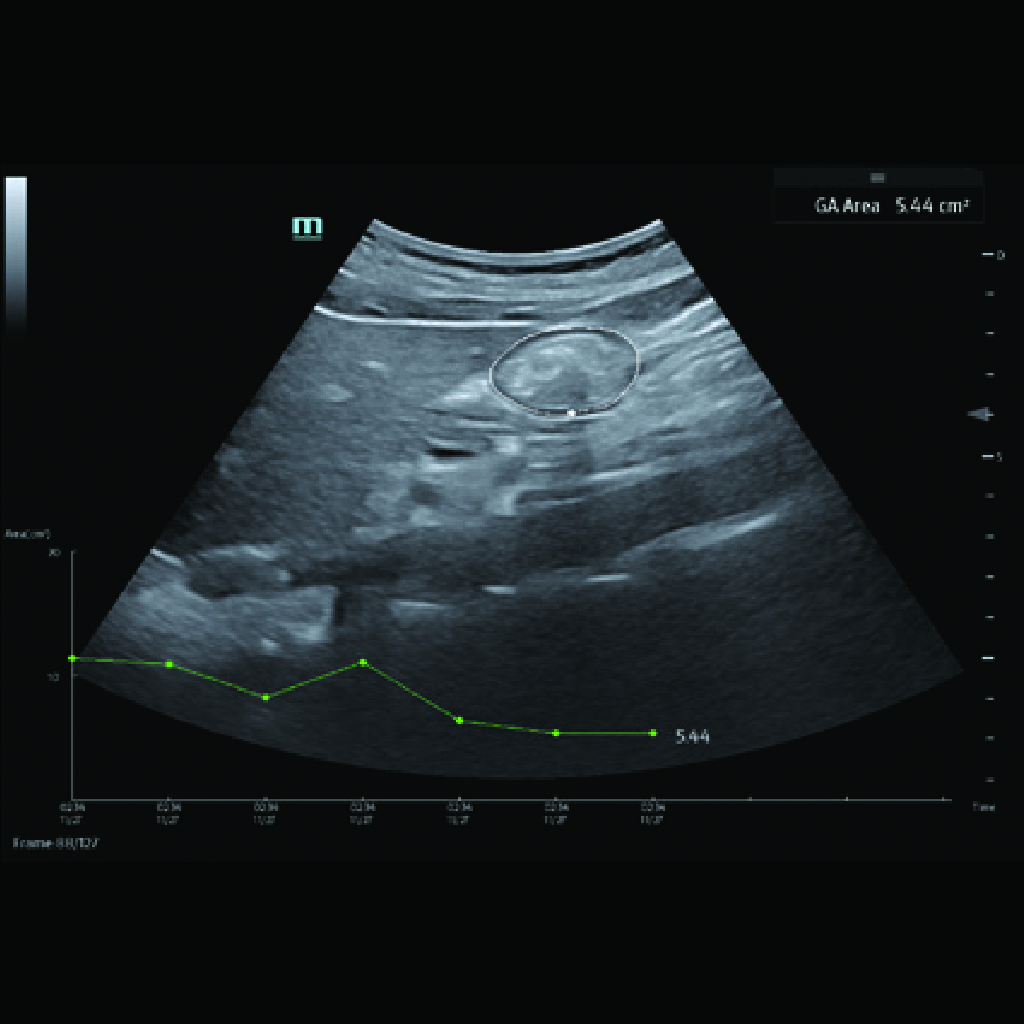

Функция, предназначена за автоматично определяне на гестационната възраст на плода по време на акушерски ултразвукови изследвания. Чрез анализиране на специфични биометрични измервания на плода, софтуерът Auto GA изчислява приблизителна гестационна възраст, което помага на лекарите да проследят развитието на плода и да оценят прогресията на бременността.